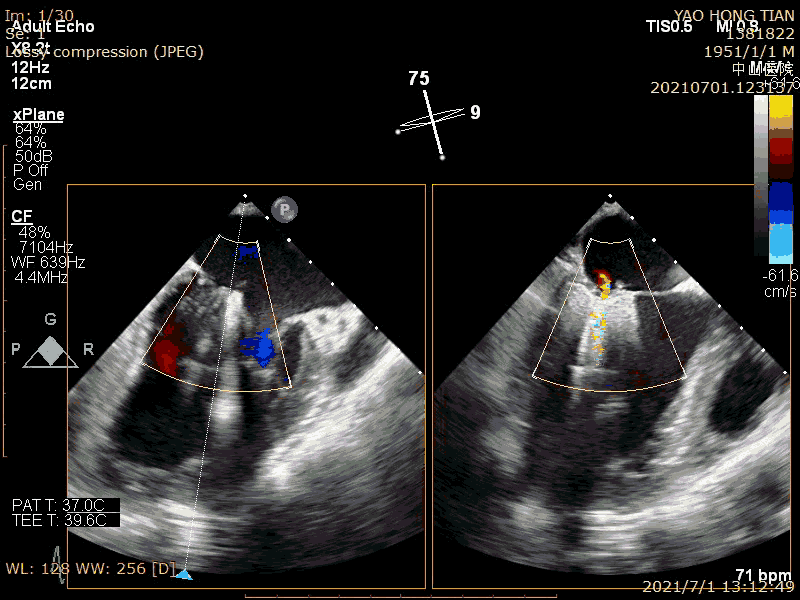

患者,男,70岁。术前超声诊断:左心室射血分数 LVEF 58%,左心室舒张末内径LVDD 52mm,左心房内径LAD 57mm,PASP 63mmHg,二尖瓣瓣尖错位导致重度二尖瓣反流,VC 6*13mm,反流面积19.8cm²(图1-2)。

术前大量反流(VC 6*13mm)

瓣尖错位导致A2P2大量反流